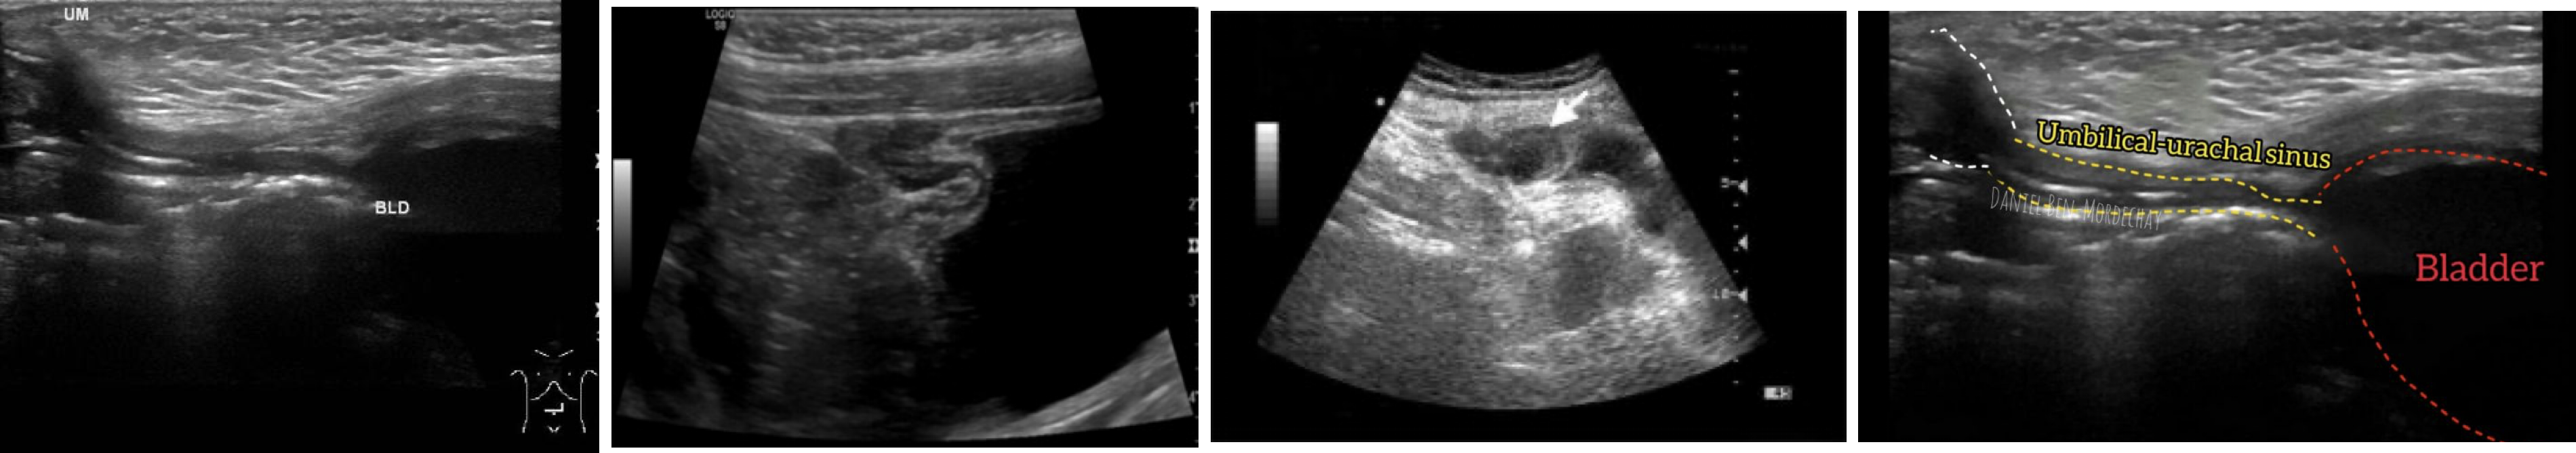

Urachal Sinus

요막관의 제대 쪽 끝부분만 개존, 맹관 형태.

임상 특징: 제대에서 점액·농성 분비물 분비, 감염 시 발적·통증

치료: 절제